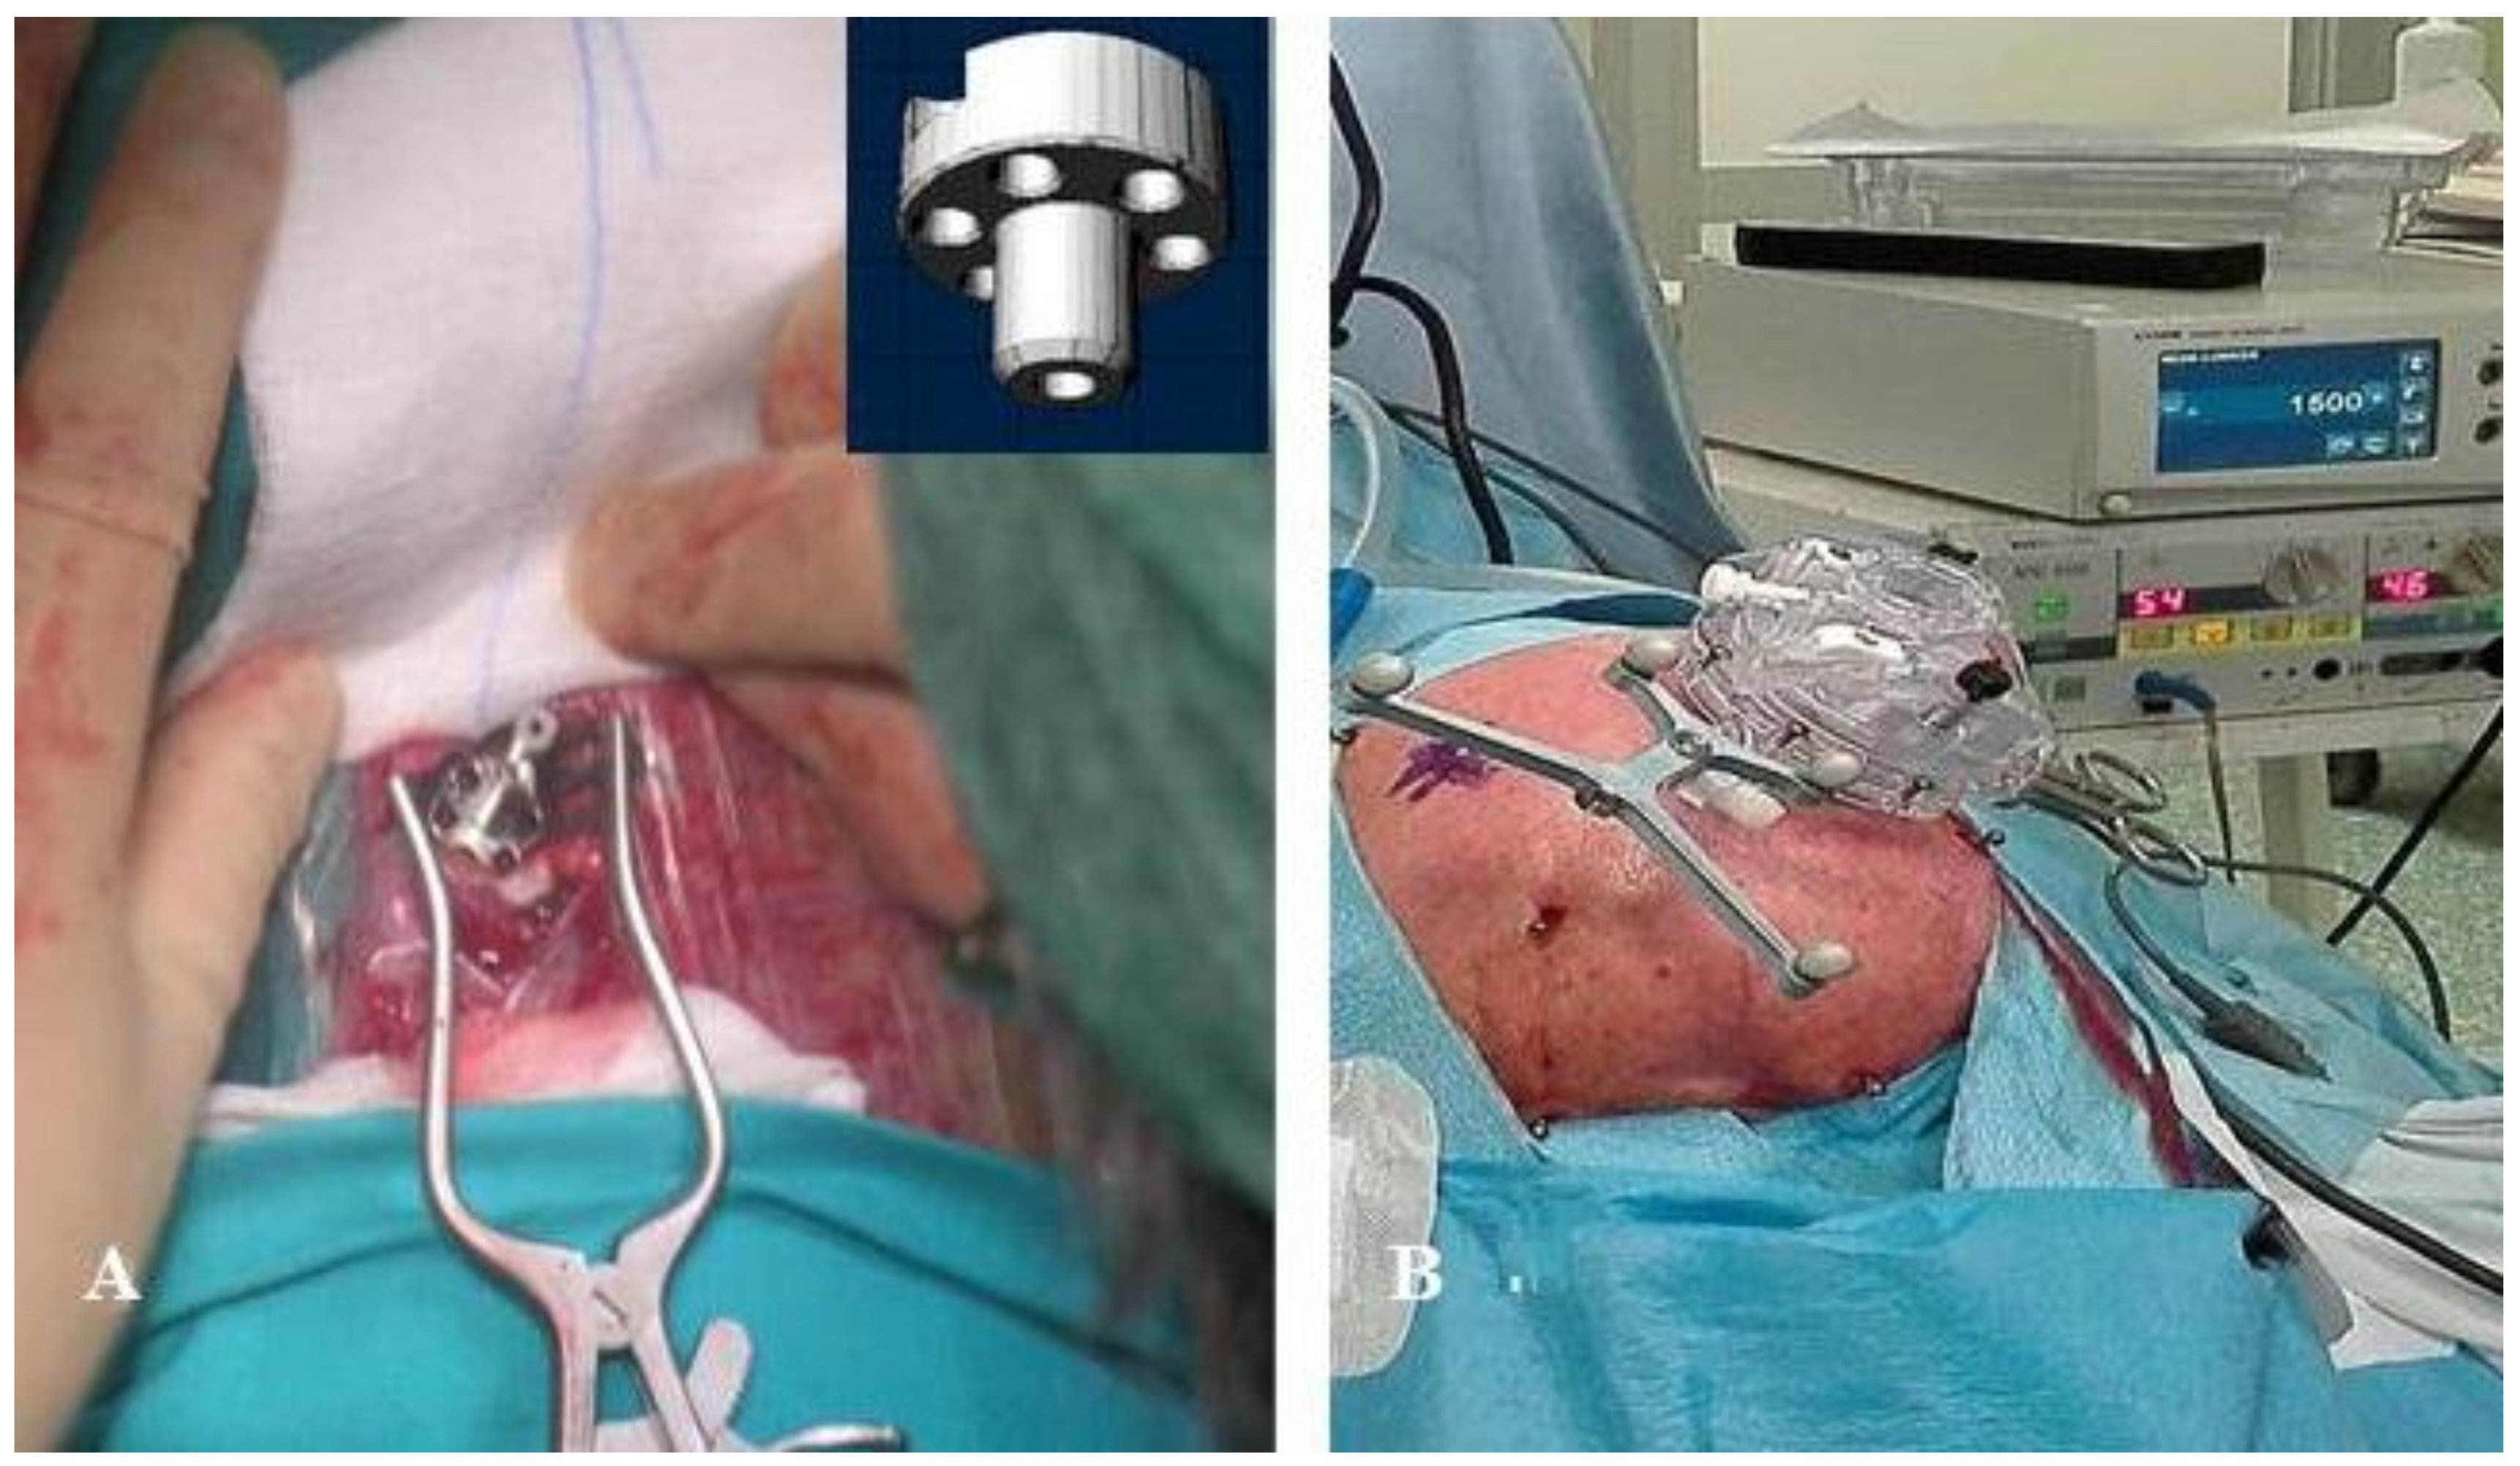

With this in mind, we started our work with frameless functional neurosurgery in 2005 after ourselves developing a device that may be applied to the skull [12,13] (Figure 1A). Starting in 2016, we adopted the Nexframe® (Nexframe® DB2040; Medtronic Neurological Division, Minneapolis, MN, USA) for deep brain stimulation (DBS) of the STN (Figure 1B) [14,15,16]. This system is advantageous and safe for the implantation of electrodes in the STN, as reported by other groups [4,17,18,19]. The implantation of electrodes may be achieved without causing patients the discomfort produced by traditional frames that must usually be worn at least the night before surgery. The Nexframe may also be utilized if one wants to use intraoperative microrecordings of neuronal activity (IOMERs) [5] or somatosensory-evoked potentials (SEPs) for better identification of the structures that are to be targeted [20,21].

Figure 1.

(A) The arch-less device, first used in 2001 [1], that could be applied to the skull using the Maranello Stereotactic System; (B) The Medtronic Nexframe DB2040.